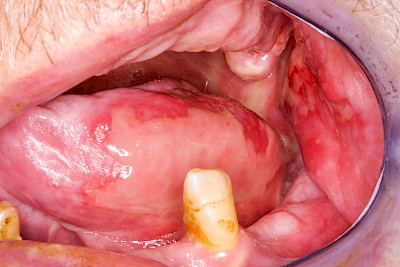

Rötung, Blutung, Verletzung

Gaumen, Wange & Zunge

Rötungen sind grundsätzlich als Anzeichen einer Entzündung zu werten.

Die 5 klassischen Entzündungszeichen:

- Rötung (Rubor)

- Schmerzen (Dolor)

- Schwellung (Tumor)

- Wärme (Calor)

- gestörte Funktion (Functio laesa)

Einbiss & Bluterguss

Blutungen & Blutergüsse sind in den meisten Fälllen als ein Zeichen einer Verletzung wie z.B. einem Einbiss oder nach einem Sturz zu werten.

Kauen auf Wange, Zunge & Lippen

Das Kauen auf Wange, Zunge oder Lippen zählt zu den sogenannten Habits und ist meist stressbedingt. Diskrete Linien (Verhornungsleisten) oder aber unruhige Schleimhautareale bis hin zu Erscheinungsformen wie "wildes Fleisch" können dabei auffallen.